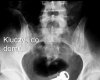

Ludzie to niesamowity gatunek. Potrafią tworzyć niesamowite rzeczy, ale jednocześnie potrafią być równie skretyniali co inteligentni. Mamy dla Was galerię niesamowitych szpitalnych zdjęć rentgenowskich na których uwieczniono człowieka i narzędzie zbrodni. Nigdy nie uwierzycie jakie przedmioty ludzie wkładają sobie w tyłek!